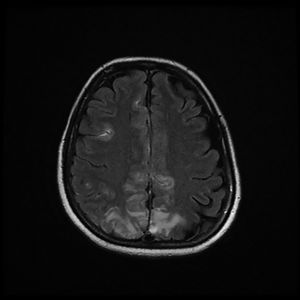

The patient was discharged to the ward on the fifth day, where inattention, apathy, and asymmetric mobilization of the right lower limb were noted. Although she showed steady respiratory and neurological improvement, a magnetic resonance imaging (MRI) study reported extensive hyperintense areas involving both the cortex and subcortical white matter. These areas were bilateral and symmetrical, but with greater extension in the right hemisphere and involvement of the parasagittal region and the bilateral parietal convexity, the bilateral frontal parasagittal region, and areas in the region of the right frontal superior convexity. Small areas of leptomeningeal uptake were identified, corresponding to slower, though unrestricted, intravascular blood flow. The finding was reported as posterior reversible encephalopathy (PRES) (Figs. 3 and 4). After the third day of hospitalisation, the patient presented episodes of HT, which were initially treated with labetalol and later with enalapril and amlodipine, and were diagnosed as peripartum hypertension. Nine days after re-admission to the ward the patient was discharged home after a total hospital stay of 18 days. Enalapril, amlodipine, and levetirazetam were prescribed as outpatient treatment.

Magnetic resonance imaging (T2-weighted and FLAIR images): Axial slices showing hyperintense areas with bilateral cortical and subcortical white matter involvement, more extensive in the right hemisphere. Involvement is seen in the parasagittal region and bilateral parietal convexity, and in the bilateral frontal parasagittal region. The image is suggestive of PRES.

None of the published cases of encephalitis have reported EEG results. Though nonspecific, the findings in our patient are compatible with viral encephalitis. Thromboembolism (common in COVID-19 patients) and cerebral haemorrhage/ischaemia had previously been ruled out with CT and angioCT without contrast. The MRI performed 2 days later (Figs. 3 and 4) with T1-weighted sequence in the sagittal plane and in T2 and FLAIR in the axial plane was compatible with PRES.